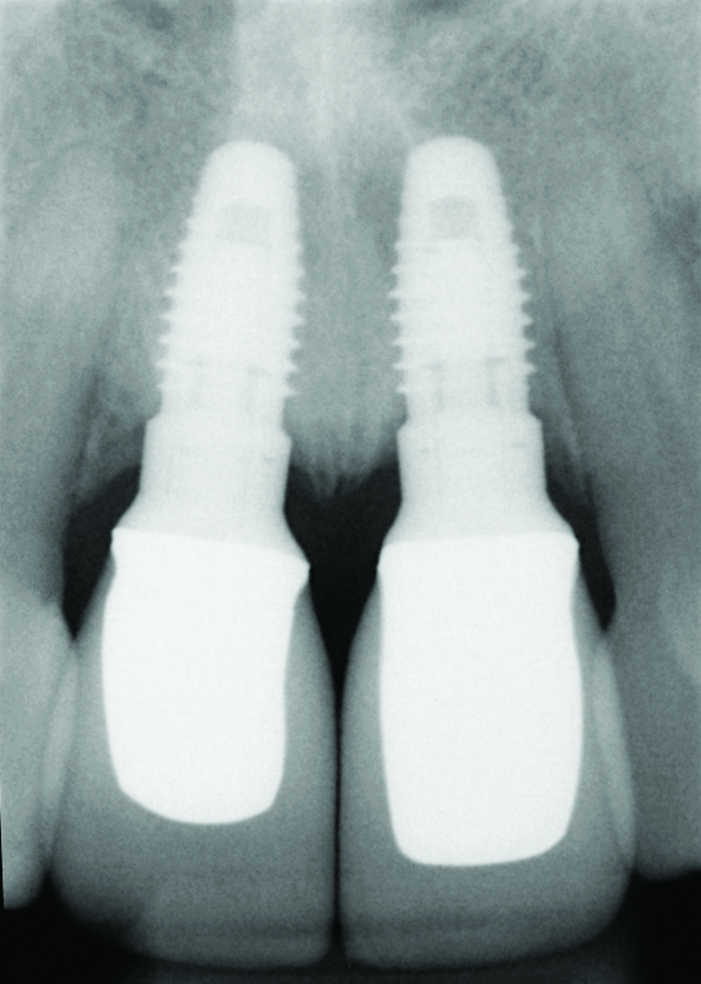

Fig 10. Ten-year radiographic follow-up of the same case.

Figure 10

Most of the literature on implant success rates has not identified a correlation with the gingival biotype, although it is increasingly accepted that the biotype and tissue volume have an important impact on the esthetic outcome and minimizing the risk for post-restoration tissue instability. In Figure 9 and Figure 10, adjacent implants placed 10 years previously are successful in terms of integration, but negative soft-tissue changes—both facial and inter-implant—have resulted in poor esthetics due to recession and soft-tissue color changes from titanium shine-through.14,15 Tissue color is less impacted by transmucosal restorative materials when greater than 3 mm thick, but this thickness is rarely seen in the transmucosal area, even in grafted cases.16,17